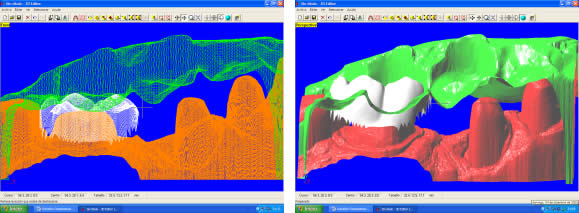

Introducción.- En oclusión, existen varios campos de aplicación básica para la digitalización. Hablamos, preferentemente, de la digitali- zación tridimensional. Recordemos que esta palabra es sinónimo de medición y –como tal- auxilio en esta rama odontológica tan necesitada de precisión. La digitalización tridimensional consistirá en el registro de la posición espacial, de un finito número de puntos, determinando sus coordenadas -x,y,z-. A menor distancia entre cada punto se conseguirá como resultado un objeto virtual con mayor detalle, coincidente con el real. Con cada triada se podrá formar una superficie, que continuada con la generada por el resto de la malla de puntos, completarán la forma del objeto. Este es el origen de donde partimos para establecer el concepto básico de las revolucionarias aplicaciones 3D. Se parte así del denominado escaneado tridimensional: Escaneado Superficial de un objeto real -> “Nube de Puntos” -> “Malla de Alambre” -> Superficie del Objeto Virtual. Con los modelos dentarios, impresiones o registros de oclusión, virtuales (en la pantalla del ordenador), realizaremos ahora, mediante un programa informático, la manipulación simulada, mediante computadora, para la realización del estudio y diseño de la oclusión. La Oclusión Computarizada (OC) –dentro de la más amplia Odontología Computarizada- comprende, hoy, fundamentalmente, tres fines: 1º)- El Estudio, Diagnóstico y Plan de Tratamiento Asistidos por Ordenador. 2º)- El Encerado Computarizado. (Por RP –Rapid Prototyping-, Prototipado Rápido, o por CAM –Computer Assisted or Aided Machining or Manufacturing-, Maquinado Asistido o Ayudado por Computador). 3º)- La Restauración y Confección de Prótesis Computarizada. (Por CAD-CAM, -Computer Assisted Design – Computer Assisted Manufacturing-, Diseño y Fabricación Asistidas por Computador). La Odontología Computarizada tiene entre sus numerosas secciones, ésta de oclusión, considerada primordial en el trabajo clínico habitual, desde la que nos relacionamos con la ortodoncia, cirugía implantológica, tecnología protésica y prostodoncia. Cada uno de los citados fines de la OC necesita partir de un escaneado tridimensional de los objetos a tratar: elementos del sistema dentario (arcadas) –de forma directa, en la misma boca del paciente-, o modelos dentales obtenidos por una impresión material de éstas y su posterior escaneado –o forma indirecta, fuera de la boca del paciente-. El escaneado se puede realizar con variados dispositivos, resultando procedimientos de distintos tipos y con diferentes características, clasificados simplificadamente como: A) Escaneado de contacto, háptico: B) Escaneado sin contacto: Tomando una imagen del objeto, marcado por líneas o cuadrículas luminosas proyectadas sobre su superficie, que se deforman con ella, analizándose luego digitalmente. El escaner se considera aquí un analizador trigonométrico del objeto, que registra su imagen, marcada mediante un rayado por luz –normalmente láser- (que permite, mediante software, obtener las coordenadas espaciales de multitud de puntos, que son agrupados en unidades de tres, constituyendo los vértices de una superficie triangular, que sumándose a las vecinas, llegarán a representar la envuelta completa del objeto y así su forma volumétrica o tridimensional). C) Combinado. Externo e Interno. Los escáneres suelen resultar, actualmente, poco económicos, y aunque van decreciendo en coste, están –para estas fechas- en un nivel que suele partir como mínimo de los 8.000 euros; siempre dependiendo del procedimiento de registro empleado, tamaño y precisión del escaneado. Existen: A) aparatos integrados en sistemas dentales, desarrollados específicamente para nuestro campo, de comprobada eficacia y de alto coste económico; B) dispositivos de uso general, aplicables a los propósitos de la odontología, de complicada adaptación pero de muy bajo coste relativo; C) múltiples posibilidades para la construcción de un escaner propio, casero y económico, que pueda, con suficiente experiencia, llegar a funcionar para uso profesional, gracias a la existencia de suficiente información de la tecnología empleada, ampliamente divulgada y de fácil desarrollo; útiles para fines diagnósticos. En oclusión necesitamos el 3D, pero también el 4D. Sumamos aquí a las tres coordenadas espaciales de cada punto del objeto, otra más, la cuarta dimensión: el tiempo. Dado que un objeto móvil, lo es por la temporalidad de sus posiciones en el espacio. Así se registrarán y analizarán digitalmente los movimientos mandibulares para conseguir la articulación y reproducción de la función masticatoria. Para esto se han aplicado determinados registros, mediante sensores de posición o por receptores de actividad muscular, como los electromiógrafos, o el más específico articulador virtual, del que se encuentran diferentes productos de software, englobados –como complemento necesario- en los programas que acompañan a los distintos sistemas de cad-cam dental. Desde el escaneado, o transformación u obtención del objeto real en cuerpo 3D, numérico, adquirido para ser estudiado y manipulado de forma digital, virtual, en el computador, continuamos con otras vías, ahora posibles, de enorme potencial, desde el estudio y planificación a la fabricación protésica. Así van a ser expuestas a continuación: A) La planificación; B) el encerado; y C) la fabricación. A) -Estudio, Diagnóstico y Plan de Tratamiento Asistidos por Ordenador. La planificación de la rehabilitación oclusal, puede iniciarse: A-1) Por Registro Estático Morfológico Computarizado, del aparato estomatognático y sistema dentario. Que puede realizarse: I) A partir de Escaneado Extraoral. I-a) Escaneado Volumétrico (CT–tomografía computarizada-) (O mejor, CBCT –tomografía computarizada de haz cónico-, de menor radiación y coste, con aparatos diseñados específicamente para uso dento-máxilo-facial ). I-b) Escaneado Superficial –de los modelos de estudio- y Registros Oclusales-. II) A partir de Escaneado Intraoral. II-a) Escaneado Volumétrico (CT local, o CBCT local, que se están desarrollando para aplicación retroalveolar). II-b) Escaneado Superficial –de las caras oclusales del sistema dentario-. A-2) Por Registro (Estático Morfológico Computarizado) de Huellas de Oclusión (o Registros Oclusales), para análisis de contactos intermaxilares, estáticos -y menos o indirectamente los movimientos mandibulares-. Mediante escaneado superficial de registros, sus modelos 3D, y combinación o no, con el Papel de Articular Electrónico (T-Scan). A-3) Por Registro Dinámico Funcional (fisiológico) Computarizado: I) Registro Computarizado (Integrado) de los Movimientos Mandibulares –electropantográfico o cinematográfico-. Por sensores o marcadores de posición. II) Registro Computarizado (Integrado) de la Función Muscular –electromiográfico-. A-4) Por Integración Informática de varios de los Registros citados. B) -Encerado Computarizado. Es el modelado o diseño virtual en la pantalla del ordenador y su realización en material de patronaje (como la cera u otro de similar; económico, modificable, transformable y rápido), que puede realizarse por: B-1) Por RP –prototipado aditivo- o B-2) por CAM –maquinado sustractivo-. Como pensamos en el concepto clásico, la realización de un encerado diagnóstico es clave para una rehabilitación oclusal correcta. Además el encerado servirá para la confección de: a) una posible férula radiológica y quirúrgica, b) una referencia para el tallado, la prótesis o rehabilitación temporal y el patrón para la definitiva. Se llevará a cabo, en dos etapas: 1ª) Etapa de creación del patrón. Elaboración virtual en la pantalla del ordenador. Necesitando el software apropiado, CAD. 2ª) Etapa de confección. Elaboración Real, mediante RP o CAM. 1ª) La etapa de creación virtual del patrón en la pantalla del ordenador, mediante un programa informático de diseño y manejo de objetos tridimensionales, (siempre partiendo de un registro previo, como el escaneado de los modelos), puede facilitarse con varias herramientas para: -Elaboración Virtual por Adición. 2ª) La etapa de confección, o elaboración real, mediante RP o CAM. -Confección por RP (Rapid Prototyping) –Prototipado Rápido-, de adición o construcción capa a capa, añadiendo una sustancia que se endurece, aumentando su nivel en superficie. La elaboración real por adición, es posible en un variado –pero limitado- tipo de materiales. -Confección por CAM (Computer Aided Machining) –Maquinado o Tallado Asistido por Ordenador-, de eliminación de sustancia o esculpido en un bloque sólido. La elaboración real por sustracción, es posible en un numeroso -y casi ilimitado- tipo de materiales. Existen gran cantidad de dispositivos que consiguen la fabricación y consecución física de un encerado real, a partir de su elaboración virtual, desde un escaneado y su diseño computarizado. Todos los sistemas denominados de cad-cam dental, en general, aunque no estén espe- cialmente dispuestos para ello, pueden dedicarse a este propósito; simplemente colocando un material de patronaje, como la cera, en lugar del material con el que se constituirá la prótesis definitiva. Pero, existen –también- sistemas espe- cialmente configurados para el trabajo en material de diseño, normalmente: ceras, resinas o compuestos, es lo que se denomina prototipado rápido (rapid prototyping). En la industria general, la fabricación de cualquier objeto en serie, requiere de estos procedimientos en las primeras etapas de elaboración para su producción. La más económica y reducida Impresora 3D o Sistema de Prototipado Rápido, que puede confeccionarnos unos maxilares, a partir de la tomografía, o un encerado diagnóstico, según el software disponible. Su precio actual 45.000 Euros. C) -Restauración y Confección de Prótesis Computarizada. (Por CAD-CAM). Es el modelado o diseño virtual en la pantalla del ordenador y su realización en material definitivo (como porcelana, titanio, aleación preciosa, u otro similar); poco económico, difícilmente o no modificable, ni transformable y que requiere de un tiempo adecuado, mucho mayor que el requerido para la confección del patrón de material plástico. Esto puede realizarse por numerosos dispositivos. Existen gran variedad de sistemas para el diseño y confección de restauraciones y prótesis. Son los denominados gene- ralmente SISTEMAS DE CAD-CAM DEN- TAL (Dental Cad-Cam System): (Entre estos sistemas encontramos los que también pueden planificar el tratamiento restaurativo y realizar el encerado diagnóstico con diseño y confección de un patrón oclusal; como hemos referido antes). Históricamente estos sistemas comenzaron con la década de los setenta -en 1971, con el Holodontography-Altschuler System-, y con el Sopha System de Duret, progresando enormemente hasta comienzos de los noventa. Durante esos veinte años, se potenció su desarrollo con el siguiente hito histórico que los encumbró, en su segunda década, por la aparición de los principales impulsores del cad-cam clínico comercializable -Mörmann y Brandestini, en 1981-, denominado Sistema Cerec. También se establecieron los principios de estos dispositivos con el DCS Dental System, el CAP System, el Minnesota-Rekow System, el Nissan Cad/Cam System, Automill y Microdenta System. El culmen del progreso se alcanzó a mediados de los noventa, con sistemas ampliamente comercializados y evolucionados hasta hoy: Procera, DCS Dental, o Cicero. En los siguientes diez años, se continuó perfeccionando los sistemas citados; hubo algunos sistemas no comerciales o de escasa difusión, o distribuidos moderadamente; repre- sentando un período hasta el 2000, con una pequeña depresión, en los años medios, por el declive en la extensión de estos productos, en relación al extraordinario futuro que se les auguraba, motivada por el alto coste de los equipos y las limitaciones en su potencia digital, en el que –aún y así- aparecieron sistemas como: Belledent, Cadim, Dentscan, CCD System, Cynovad, Digident-Girrbach, Decim y Etkon. La segunda revolución para la odontología por cad-cam se produjo con el comienzo del siglo. Ampliándose enormemente la cantidad de sistemas y alentándose una explosión del trabajo digital en odontología, con: Cercon-Degussa, Lava-3M-Espe, Cad-Esthetics System-Ivoclar, DDS, GC-Dental, Everest-Kavo y Bego. En estos momentos el futuro de la odontología se encuentra inexorablemente unido a estos aparatos. Para el clínico o el laboratorio dental es hoy imprescindible contar con ellos. Siguen nuevas apariciones, como el sistema Hint-Els, o el Evolution-4D, similar al Cerec, que fue el pionero, pero que todavía, a la fecha, se mantiene como el más versátil, modulable y práctico, con progresos como el facilitado trabajo de diseño tridimensional o el nuevo escaneado extraoral independiente. Los sistemas de cad-cam, están integrados por: un escaner que digitaliza el objeto dental, un ordenador con el software adecuado para el diseño virtual, y una máquina de tallado para la fabricación del objeto diseñado en un material determinado. Una relación actualizada, de gran número de los sistemas existentes se encuentra en “Aktuelle CAD/CAM Systeme”, en http://www.tu-dresden.de/medprothetik/computerzahn/CAD-CAM-Systeme.htm Factores clave en la Oclusión Computarizada-. La digitalización del estudio, diagnóstico y tratamiento de la oclusión, como la construcción o restauración de un sistema dentario óptimo para la correcta función masticatoria del aparato estomatognático, pretende facilitar y generalizar la excelencia en el trabajo clínico. Es una aplicación de preferencia informática porque pueden manejarse gran cantidad de datos, mediciones, relaciones geométricas, unidas a la tridimensionalidad y la movilidad de sus elementos, de una forma racional, lógica y científicamente fundamentada, aún partiendo de concepciones filosóficas o criterios sujetos a distintas escuelas de oclusodoncia. La digitalización de la oclusión pude llevar- nos a despejar supuestos sin evidencia científica, de la que adolece sectorialmente nuestro arte. Tenemos suficientes fórmulas, reglas y relaciones numéricas, aportadas por numerosos autores, que tienen que se recopiladas y que pueden así ser aplicadas. Yá que la digitalización recoge todos los datos métricos y posicionales (coordenadas de cada punto, con su x,y,z), del sistema dentario, se pueden establecer fórmulas matemáticas para que -siendo la z la determinante de la altura de un punto en el espacio-: una z máxima, de una pieza mandibular, esté más o menos próxima a una z mínima de una pieza maxilar; que un punto (de cúspide) -con una determinada x,y- maxilar, coincida con otro –con la misma x,y- mandibular, pero con distintas aunque casi idénticas z, dándose el contacto oclusal. Y de esta forma, con sucesivas relaciones (matemáticas) se construiría una oclusión tendente a la excelencia; matemáticamente desarrollada. Así podría confeccionarse, automáticamente, una oclusión geométrica, dando, por ejemplo, solamente: la posición base de cada pieza, la x,y de las cúspides de una hemiarcada, y la altura de su plano oclusal, y automáticamente se generarían las cúspides agonistas y antagonistas, y la morfología dental completa de ambas arcadas. Se tendrían que añadir los datos correspondientes a los dientes anteriores, a las ATMs y las fórmulas de relación de las pendientes. Distintos autores han desarrollado relaciones métricas en oclusión. Algunos han simplificado el proceso, como partida, para ir añadiendo variantes; así, pueden usarse valores standard, normales, del ángulo cuspídeo para fabricar la morfología oclusal en CAD/CAM, -cuando la creación del esquema oclusal es de novo-, según Hobo y Takayama; y el uso de varios valores fijos de partida, universalmente aceptados, en lugar de la medida directa de la pendiente condilar es, según los mismos autores, muy importante en el desarrollo extenso de los sistemas de CAD/CAM. Así, el procedimiento de «twin-stage» propuesto por estos autores, en su libro “Oral Rehabilitation”, proporciona una solución en la producción de una oclusión dinámica tridimensional para el CAD/CAM. Otra técnica, consiste en el encerado virtual, mediante un modelado CAM, siguiendo las etapas de Shillimburg, o Kuwata, elaborando paso a paso la morfología oclusal, orientada a su enfrentamiento con el antagonista, encaminando los volúmenes cuspídeos como en el encerado progresivo clásico, gota a gota. Se realizaría su construcción virtual en la pantalla del ordenador, pudiendo estar facilitada su manipulación, mediante “espátulas de encerado virtual”, utilizando los digitalizadores de brazo articulado, con los que se pueden disponer los volúmenes necesarios, en la posición espacial que se desee. No obstante, el modelado dental se puede realizar siempre, aunque sea a través del clásico ratón del ordenador, de forma virtual, con la imagen tridimensional en la pantalla, utilizando diferentes procedimientos, con el software adecuado: A) Automático, a partir de las reglas dentométricas, odontométricas y cefalométricas, relacionadas con la gnatología, tomando previamente los valores claves necesarios del paciente. B) Mediante diseño de la anatomía con trazado de los perfiles, líneas y curvas, que van a definir las superficies dentales. Trabajando bidimensionalmente, en base a cortes de la estructura a construir, que manipulada variando sus dos dimensiones, va a corresponderse con la morfología dental tridimensional, al establecerse un área de influencia y cambio en los cortes vecinos, y así alterándose el volumen dental completo. Este era el procedimiento de variación anatómica utilizado, durante dos décadas con el Sistema Cerec (el Cerec 1, Cerec 2 y Cerec 3), hasta la llegada del Cerec 3D. C) Mediante copiado de la cara oclusal ideal, realizada previamente en cera u otro material real, del diente, su registro oclusal o su antagonista, en el concepto original del Sistema CEREC, de construcción oclusal mediante Correlación –copiando un encerado previo- o Función –correspondiendo automáticamente a la cara oclusal del antagonista-. D) Mediante selección de dientes, individuales o en grupo (incisivos, caninos, premolares, molares, arcadas, hemiarcadas, sistema dentario, maxilares o mandibulares), de entre un grupo de archivos de modelos dentales tridimensionales virtuales, como una librería de objetos 3D. Como en la selección de las tablillas de dientes para la confección de las prótesis completas. Escogiendo tamaño y forma. Colocando cada pieza o bloque en su lugar, con la disposición espacial y oclusal correspondiente. E) Mediante la misma selección, antes citada, seguida luego de una transformación, como estiramiento o estrechamiento, u otras variaciones morfológicas, con las herramientas de edición del programa informático, hasta conseguir la oclusión que se pretende. F) Mediante encerado virtual, de adición progresiva de volúmenes anatómicos, en el concepto clásico de encerado gota a gota, con la metódica de P. K. Thomas, para restauraciones parciales, o de Kuwata, para rehabilitaciones extensas. El método de encerado es el que nos permitirá la construcción de una oclusión individualizada. Pero la necesidad de utilización de un articulador es evidente. Es presumible que se desarrollen nuevos instrumentos para la perfección de la oclusión computarizada, semejantes a los articuladores mecánicos tradicionales. Serán los denominados articuladores virtuales, (VA –Virtual Articulator-), o simuladores digitales de la articulación oclusal, consistentes en un programa informático, capaz de relacionar los modelos virtuales, permitiendo movimientos similares a los naturales del paciente: es la aplicación de la tecnología de la realidad virtual a la oclusión (VR –Virtual Reality-). Esto es lo que nos permitirá pasar de la fórmula empleada generalmente para el modelado oclusal, que suele ser estática y referida a un registro de las superficies antagonistas, a un sistema experto que reproduzca la relación completa de ambas arcadas, las articulaciones, y su combinación con los movimientos masticatorios: realizando la dinámica mandibular. Hoy en la mayoría de los sistemas de cad-cam, los trabajos oclusales se realizan, extensamente, basados sólo en el enfrentamiento con el antagonista, sin tener en cuenta la movilidad mandibular, las guias condilares o anteriores. Es como si realizásemos un encerado oclusal sin tener en cuenta los determinantes anteriores y posteriores, y trabajásemos en un articulador, no ajustable, o simplemente en un Oclusor o Verticulator, sin giro de cierre ni desplazamientos horizontales.El articulador virtual, por software, para el diseño oclusal en la pantalla del ordenador, aún no es empleado de forma generalizada en estos sistemas, pero ya se encuentran como aplicaciones en algunos de ellos. Uno de los pioneros se utiliza en el sistema Cynovad. Aquí, directamente relacionado con la confección de un encerado oclusal. Otros dispositivos electrónicos y digitales, de registro por ordenador, que podrían combinarse con la construcción plástica de la oclusión, en cera u otro material, solo se están utilizando para diagnóstico, o como complementos a articuladores mecánicos sofisticados; así podemos encontrar programas como Rosy32 Robot System (Diagnostic Articulator), de registro dinámico, el VirtSet, de diagnóstico y predicción oclusal-ortodóntica, o el ArtiKulator-Software (ver ArtiDemo), de programación virtual de un articulador, con elección del equivalente mecánico real (Sam, Artex, Kavo,…). Entre éstos, el sistema más completo desarrollado, con escaneado de modelos y registros, y correspondencia con la dinámica mandibular, obtenida por un arco facial cinemático, con sensores de posición y movimiento, es el DentCAM.Para clasificar los instrumentos de oclusión, consideramos muy completa la clasificación de los articuladores mecánicos, desarrollada en The International Workshop Occlusion, de 1972, University of Michigan: 1) Clase I – Sujetadores simples de modelos. Subdivisión A (Con movimientos verticales; Corelator, Verticulator). Subdiv. B (Con articulación de bisagra sin desplazamientos horizontales; Centric Relator). Conclusiones (parciales para esta primera parte).- El articulador virtual podría establecerse a partir del escaneado de un articulador mecánico seleccionado, a partir de un modelo construido íntegramente por CAD de forma virtual, o –idealmente- a partir de un patrón anatómico, individual, a partir de la radiología tridimensional (como la Tomografía Computarizada). A estas estructuras se les sumarán los datos necesarios para la función: relación intermaxilar –estática- (oclusal) y relación cráneo-mandibular dinámica (pendiente condílea y Bennett), con ayuda también del registro de la actividad muscular (electromiografía). A la clasificación de los articuladores antes expuesta, le podemos añadir ahora el Tipo V, constituido por los Articuladores Virtuales, o instrumentos informáticos que pueden reproducir la oclusión dental en el ámbito de la realidad virtual, que se desarrollan como programas informáticos concretos, de muy variada composición en sus elementos de software, y distintos por los diferentes tipos de registros que necesitan para su efectiva y precisa actuación. Dentro de este V grupo, a su vez, podríamos –paralelamente a la clasificación de los articuladores mecánicos-, establecer tantas subclases como las de los tipos y subclases de aquellos. Así habría de clase I, como ocurre mayoritariamente en los sistemas de Cad-Cam dental actuales, cuando utilizamos modelos dentales 3D y registros estáticos de antagonistas. Es éste el cambio que se experimentará en los próximos años, en la Oclusión Computarizada: la utilización generalizada de Articuladores Virtuales de clase III y IV. Bibliografía Cooper BC. Parameters of an optimal physiological state of the masticatory system: the results of a survey of practitioners using computerized measurement devices. Cranio. 2004 Jul;22(3):220-33. Reiss B. Occlusal surface design with Cerec 3D. Int J Comput Dent. 2003 Oct;6(4):333-42 Petrie CS, Woolsey GD, Williams K. Comparison of recordings obtained with computerized axiography and mechanical pantography at 2 time intervals. J Prosthodont. 2003 Jun;12(2):102-10. Kojima T, Sohmura T, Nagao M, Wakabayashi K, Nakamura T, Takahashi J. A preliminary report on a computer-assisted dental cast analysis system used for the prosthodontic treatment. J Oral Rehabil. 2003 May;30(5):526-31 Bernhardt O, Kuppers N, Rosin M, Meyer G. Comparative tests of arbitrary and kinematic transverse horizontal axis recordings of mandibular movements. J Prosthet Dent. 2003 Feb;89(2):175-9 Tsai HH. A computerized analysis of dental arch morphology in early permanent dentition. ASDC J Dent Child. 2002 Sep-Dec;69(3):259-65, 234 Ferrario VF, Sforza C, Serrao G, Schmitz JH. Three-dimensional assessment of the reliability of a postural face-bow transfer. J Prosthet Dent. 2002 Feb;87(2):210-5. Kerstein RB. Current applications of computerized occlusal analysis in dental medicine. Gen Dent. 2001 Sep-Oct;49(5):521-30 Kerstein RB, Wilkerson DW. Locating the centric relation prematurity with a computerized occlusal analysis system. Compend Contin Educ Dent. 2001 Jun;22(6):525-8, 530, 532 passim; quiz 536. Sohmura T, Kojima T, Wakabayashi K, Takahashi J. Use of an ultrahigh-speed laser scanner for constructing three-dimensional shapes of dentition and occlusion. J Prosthet Dent. 2000 Sep;84(3):345-52. Kerstein RB. Computerized occlusal management of a fixed/detachable implant prosthesis. Pract Periodontics Aesthet Dent. 1999 Nov-Dec;11(9):1093-102 Tarantola GJ. A computerized model for teaching various methods of positioning the condyles to centric relation. Gen Dent. 1999 May-Jun;47(3):308-12 Gsellmann B, Schmid-Schwap M, Piehslinger E, Slavicek R. Lengths of condylar pathways measured with computerized axiography (CADIAX) and occlusal index in patients and volunteers. J Oral Rehabil. 1998 Feb;25(2):146-52 Tamaki K, Celar AG, Beyrer S, Aoki H. Reproduction of excursive tooth contact in an articulator with computerized axiography data. J Prosthet Dent. 1997 Oct;78(4):373-8 Garcia Cartagena A, Gonzalez Sequeros O, Garrido Garcia VC. Analysis of two methods for occlusal contact registration with the T-Scan system. J Oral Rehabil. 1997 Jun;24(6):426-32 Matsui Y, Ohno K, Michi K, Suzuki Y, Yamagata K. A computerized method for evaluating balance of occlusal load. J Oral Rehabil. 1996 Aug;23(8):530-5 Giddon DB, Sconzo R, Kinchen JA, Evans CA. Quantitative comparison of computerized discrete and animated profile preferences. Angle Orthod. 1996;66(6):441-8 Matsui Y, Neukam FW, Wichmann M, Ohno K. A computerized method for evaluating distribution of occlusal load on implant-supported fixed cantilever prostheses. Int J Oral Maxillofac Implants. 1996 Jan-Feb;11(1):67-72 Hayashi T, Saitoh A, Ishioka K, Miyakawa M. A computerized system for analyzing occlusal relations during mandibular movements. Int J Prosthodont. 1994 Mar-Apr;7(2):108-14 Maness WL. Computerized occlusal analysis. J Can Dent Assoc. 1993 Aug;59(8):701-2 Edwards CL, Richards MW, Billy EJ, Neilans LC. Using computerized cephalometrics to analyze the vertical dimension of occlusion. Int J Prosthodont. 1993 Jul-Aug;6(4):371-6 Giannazzo E, Leonardi R, Scivoli M, Rapisardi CB, Vassallo V. [Computerized parametrization in orthognathodontics] Boll Soc Ital Biol Sper. 1993 Jun;69(6):373-9 Harvey WL, Osborne JW, Hatch RA. A preliminary test of the replicability of a computerized occlusal analysis system. J Prosthet Dent. 1992 May;67(5):697-700 Boening KW, Walter MH. Computer-aided evaluation of occlusal load in complete dentures. J Prosthet Dent. 1992 Mar;67(3):339-44 Reza Moini M, Neff PA. Reproducibility of occlusal contacts utilizing a computerized instrument. Quintessence Int. 1991 May;22(5):357-60 Harvey WL, Hatch RA, Osborne JW. Computerized occlusal analysis: an evaluation of the sensors. J Prosthet Dent. 1991 Jan;65(1):89-92 Palano D, Molinari G, Salvo C. [Electromyography and computerized magnetic gnathokinesiography in the diagnosis and therapy of craniomandibular disorders] Minerva Stomatol. 1990 Dec;39(12):977-87